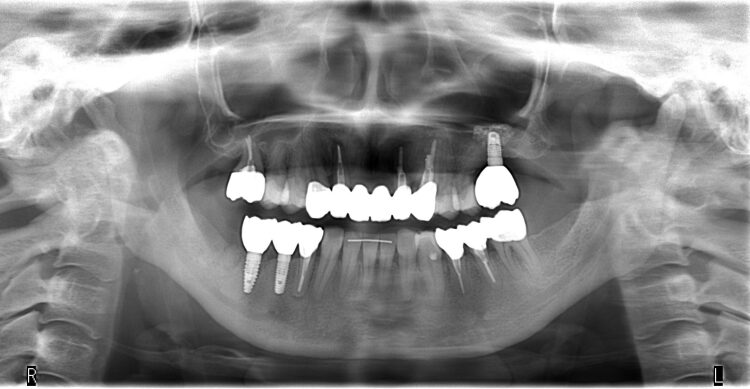

歯並びを理想的にデザインしたセットアップモデルを見ると、全体的な歯の移動量は2ミリ程度で小さく、本ケースではまず左上にインプラントを入れてから矯正を行いました。(図3)

抜く予定の歯は他にもありましたが、症状が無かったので、矯正終了までは抜かずに残しておき、矯正後に歯の移植、インプラントを追加で行い、全体のバランスをとりました。

歯並びやかみ合わせの問題は、矯正・インプラントだけで終わりではなく、可能であれば親知らずを移植することもあります。